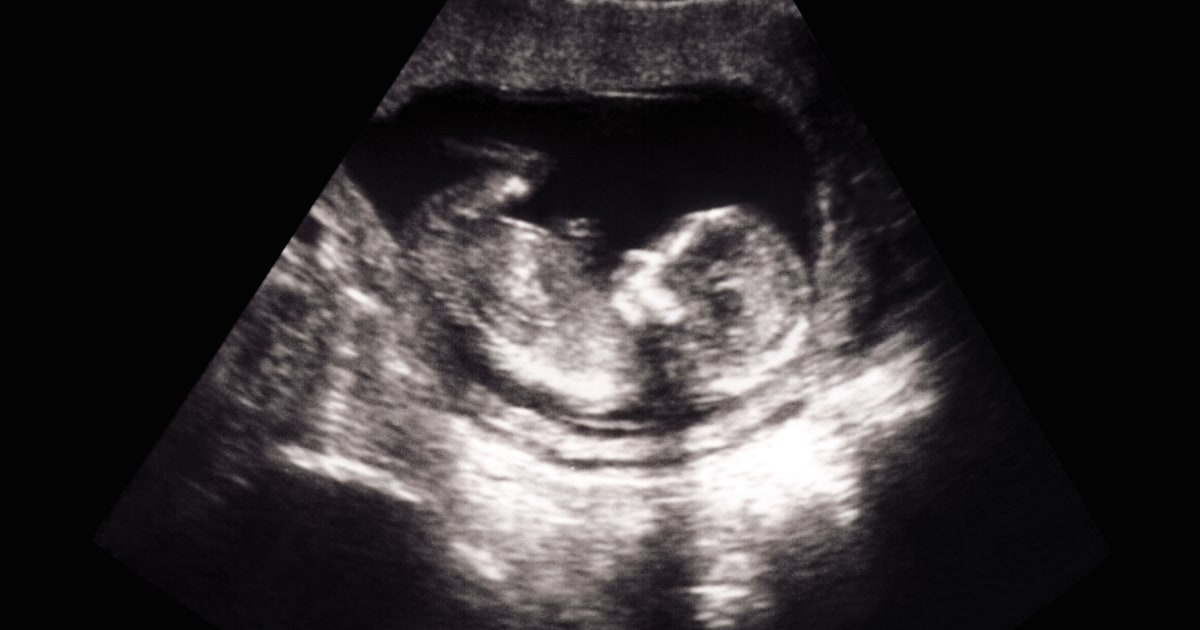

Heartbeats can be detected as early as six weeks into pregnancy, often before a person knows they are pregnant.